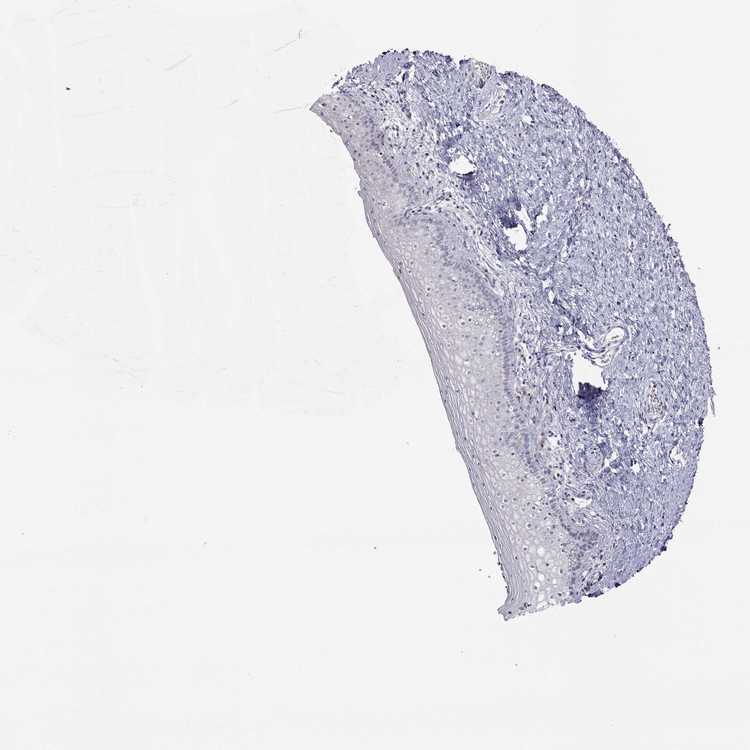

VAGINA - Antibody stainingi

Antibody staining in the annotated cell types in the current human tissue is reported as not detected, low, medium, or high, based on conventional immunohistochemistry profiling in selected tissues. This score is based on the combination of the staining intensity and fraction of stained cells.

Each image is clickable and will lead to virtual microscopy that enables deeper exploration of all samples and also displays staining intensity scores, fraction scores and subcellular localization as well as patient and tissue information for each sample.

Antibody HPA007305Antibody HPA007306Antibody CAB000106

Squamous epithelial cells Not detectedNot detectedNot detected